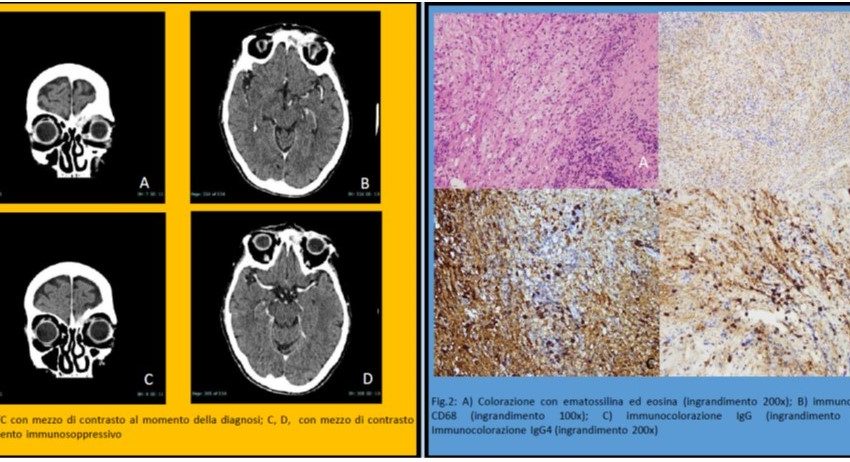

La diagnosi differenziale delle lesioni orbitali è molto complessa e varia in diverse alternative: malattia infiammatoria, sarcoidosi, granulomatosi con poliangite, morbo di Graves, linfoma, infezioni del tessuto orbitale, sindrome di Sjögren primaria, xantogranuloma, malattie di Erdheim-Chester e Rosai-Dorfman. 7, 9 Gli esami di routine del sangue e delle urine, gli esami di funzionalità epatica e renale hanno evidenziato un’anemia da carenza di ferro. La radiografia del torace è stata insignificante. La tomografia computerizzata (TC) con mezzo di contrasto ha evidenziato una neoformazione dei tessuti

molli della palpebra sinistra che erode la parete mediale dell’orbita sinistra e il processo nasale dell’osso frontale. (Fig.1) In anestesia locale è stata eseguita una biopsia incisionale della massa. Il primo esame istopatologico non è stato conclusivo: processo infiammatorio con presenza di istiociti, linfociti, granulociti e plasmacellule, con necrosi della struttura muscolare. Sono stati richiesti livelli sierici di immunoglobuline, inclusa IgG4, ed è stata eseguita una seconda biopsia in anestesia generale. Il livello sierico di IgG4 era 654 mg / dL e l’esame patologico ha evidenziato la presenza di un infiltrato

Lo screening di collo, torace, addome e bacino con TC non ha rivelato alcun coinvolgimento di altri organi. Il paziente è stato sottoposto ad esame reumatologico e successivo trattamento orale con prednisolone (35 mg / die) e azatioprina (50 mg / die) con risoluzione della proptosi e riduzione del dolore oculare. Una TC è stata eseguita dopo 4 mesi ha mostrato una riduzione della massa.